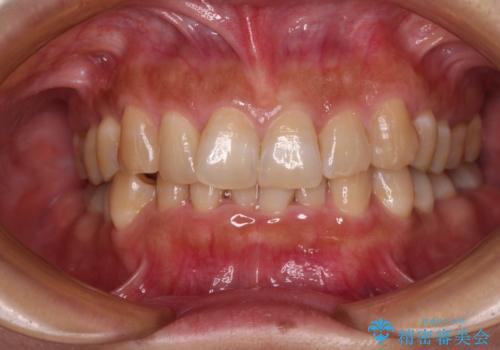

上下顎ともに歯列全体の後方移動とIPR(歯と歯の間を削る)によってデコボコが解消するように設計し、インビザラインにより治療を行うこととしました。

下顎前歯は後戻りを起こしやすいため、舌側を細いワイヤーで固定し、マウスピース型リテーナーで保定を行うこととしました。